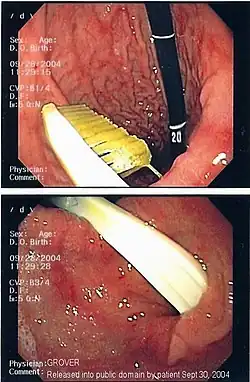

Иноро́дное те́ло (лат. corpus alienum) — с медицинской точки зрения любой чужеродный предмет, попавший внутрь организма. В узком смысле — посторонние предметы различных размеров, попавшие в глаз, ухо, нос, глотку, гортань, в пищевод или трахею (дыхательное горло), заноза.

Инородное тело, даже не повредив окружающие ткани, может стать причиной смерти. Например, в результате удушья, вызванного рефлекторным спазмом голосовых связок или непрофессиональных попыток извлечения инородного тела, приведших к гибели пациента[1], а также в результате контакта со слизистой (например, батарейка может вызвать химический ожог[2]). Дети могут засунуть мелкие предметы, например бусины, в нос или ухо[3]